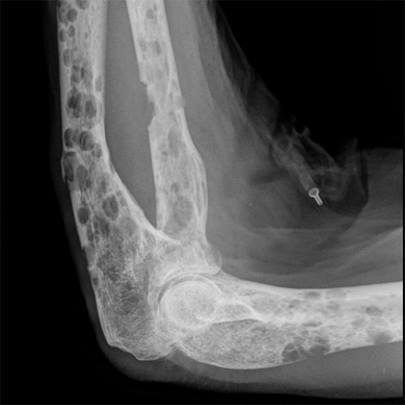

Đa u tủy là một loại ung thư máu phát triển từ tế bào tủy xương. Tế bào bình thường sẽ chuyển hóa thành tế bào máu mới, nhưng tế bào ung thư sẽ phát triển không kiểm soát và thay thế các tế bào bình thường. Điều này dẫn đến sự suy giảm chức năng của tủy xương và các bộ phận khác trong cơ thể.

- Sự suy giảm chức năng tủy xương: Bệnh nhân có thể bị suy giảm chức năng tủy xương do tế bào u tủy chiếm chỗ tủy xương.

- Đau xương: Đau xương là triệu chứng phổ biến nhất của bệnh đa u tủy. Đau có thể xuất hiện ở nhiều vị trí khác nhau trên cơ thể, nhưng thường là ở lưng, hông, và đùi.